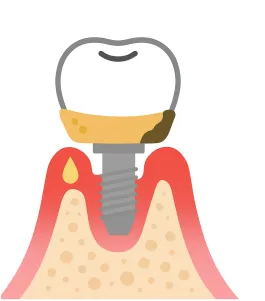

インプラント周囲炎

インプラントのリスクで最も注意すべきものが、歯周病菌への感染によって起こる「インプラント周囲炎」です。自覚症状がないまま進行し、最終的にインプラントを支える骨を溶かしてしまうことが、インプラントの寿命を縮める最大の原因です。

- 2 中期

炎症が顎の骨にまで広がり、骨が溶け始める。膿が出たり、インプラントがぐらついたりする。

- 3 末期

骨が吸収されてしまい、支えを失ったインプラントが抜け落ちてしまう。再治療が必要な状態。

当院の回避策

インプラント治療の成否は、メンテナンスにかかっていると言っても過言ではありません。当院では、治療後の定期的なプロフェッショナルメンテナンスを必須としています。セルフケアでは除去できない汚れを取り除き、周囲炎の兆候を早期に発見・対処することで、大切なインプラントを長く守ります。